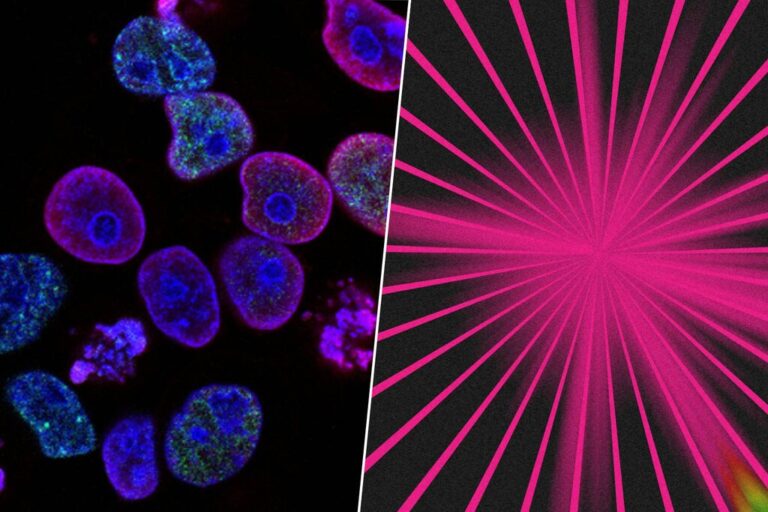

En la actualidad son muchos los grupos de investigación que tienen un objetivo muy claro: encontrar un...

El primer embarazo exitoso ha ocurrido con espermatozoides recolectados con inteligencia artificial (IA) avanzada, señalan los investigadores....

El cerebro humano contiene miles de tipos de células que se forman a partir de procesos de...

Un equipo multidisciplinar, en el que han participado investigadores y tecnólogos de varios países, ha logrado desarrollar...

Un avance médico sin precedentes podría reescribir el futuro de la reproducción asistida. Científicos del Centro de...